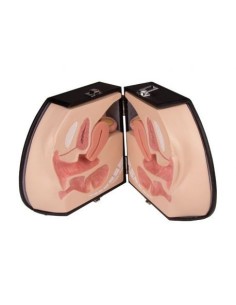

3B Modèle scientifique et gynécologique pour l'entretien avec les patientes P53

3B Scientific. Kit d'enseignement, système de reproduction femelle W40214